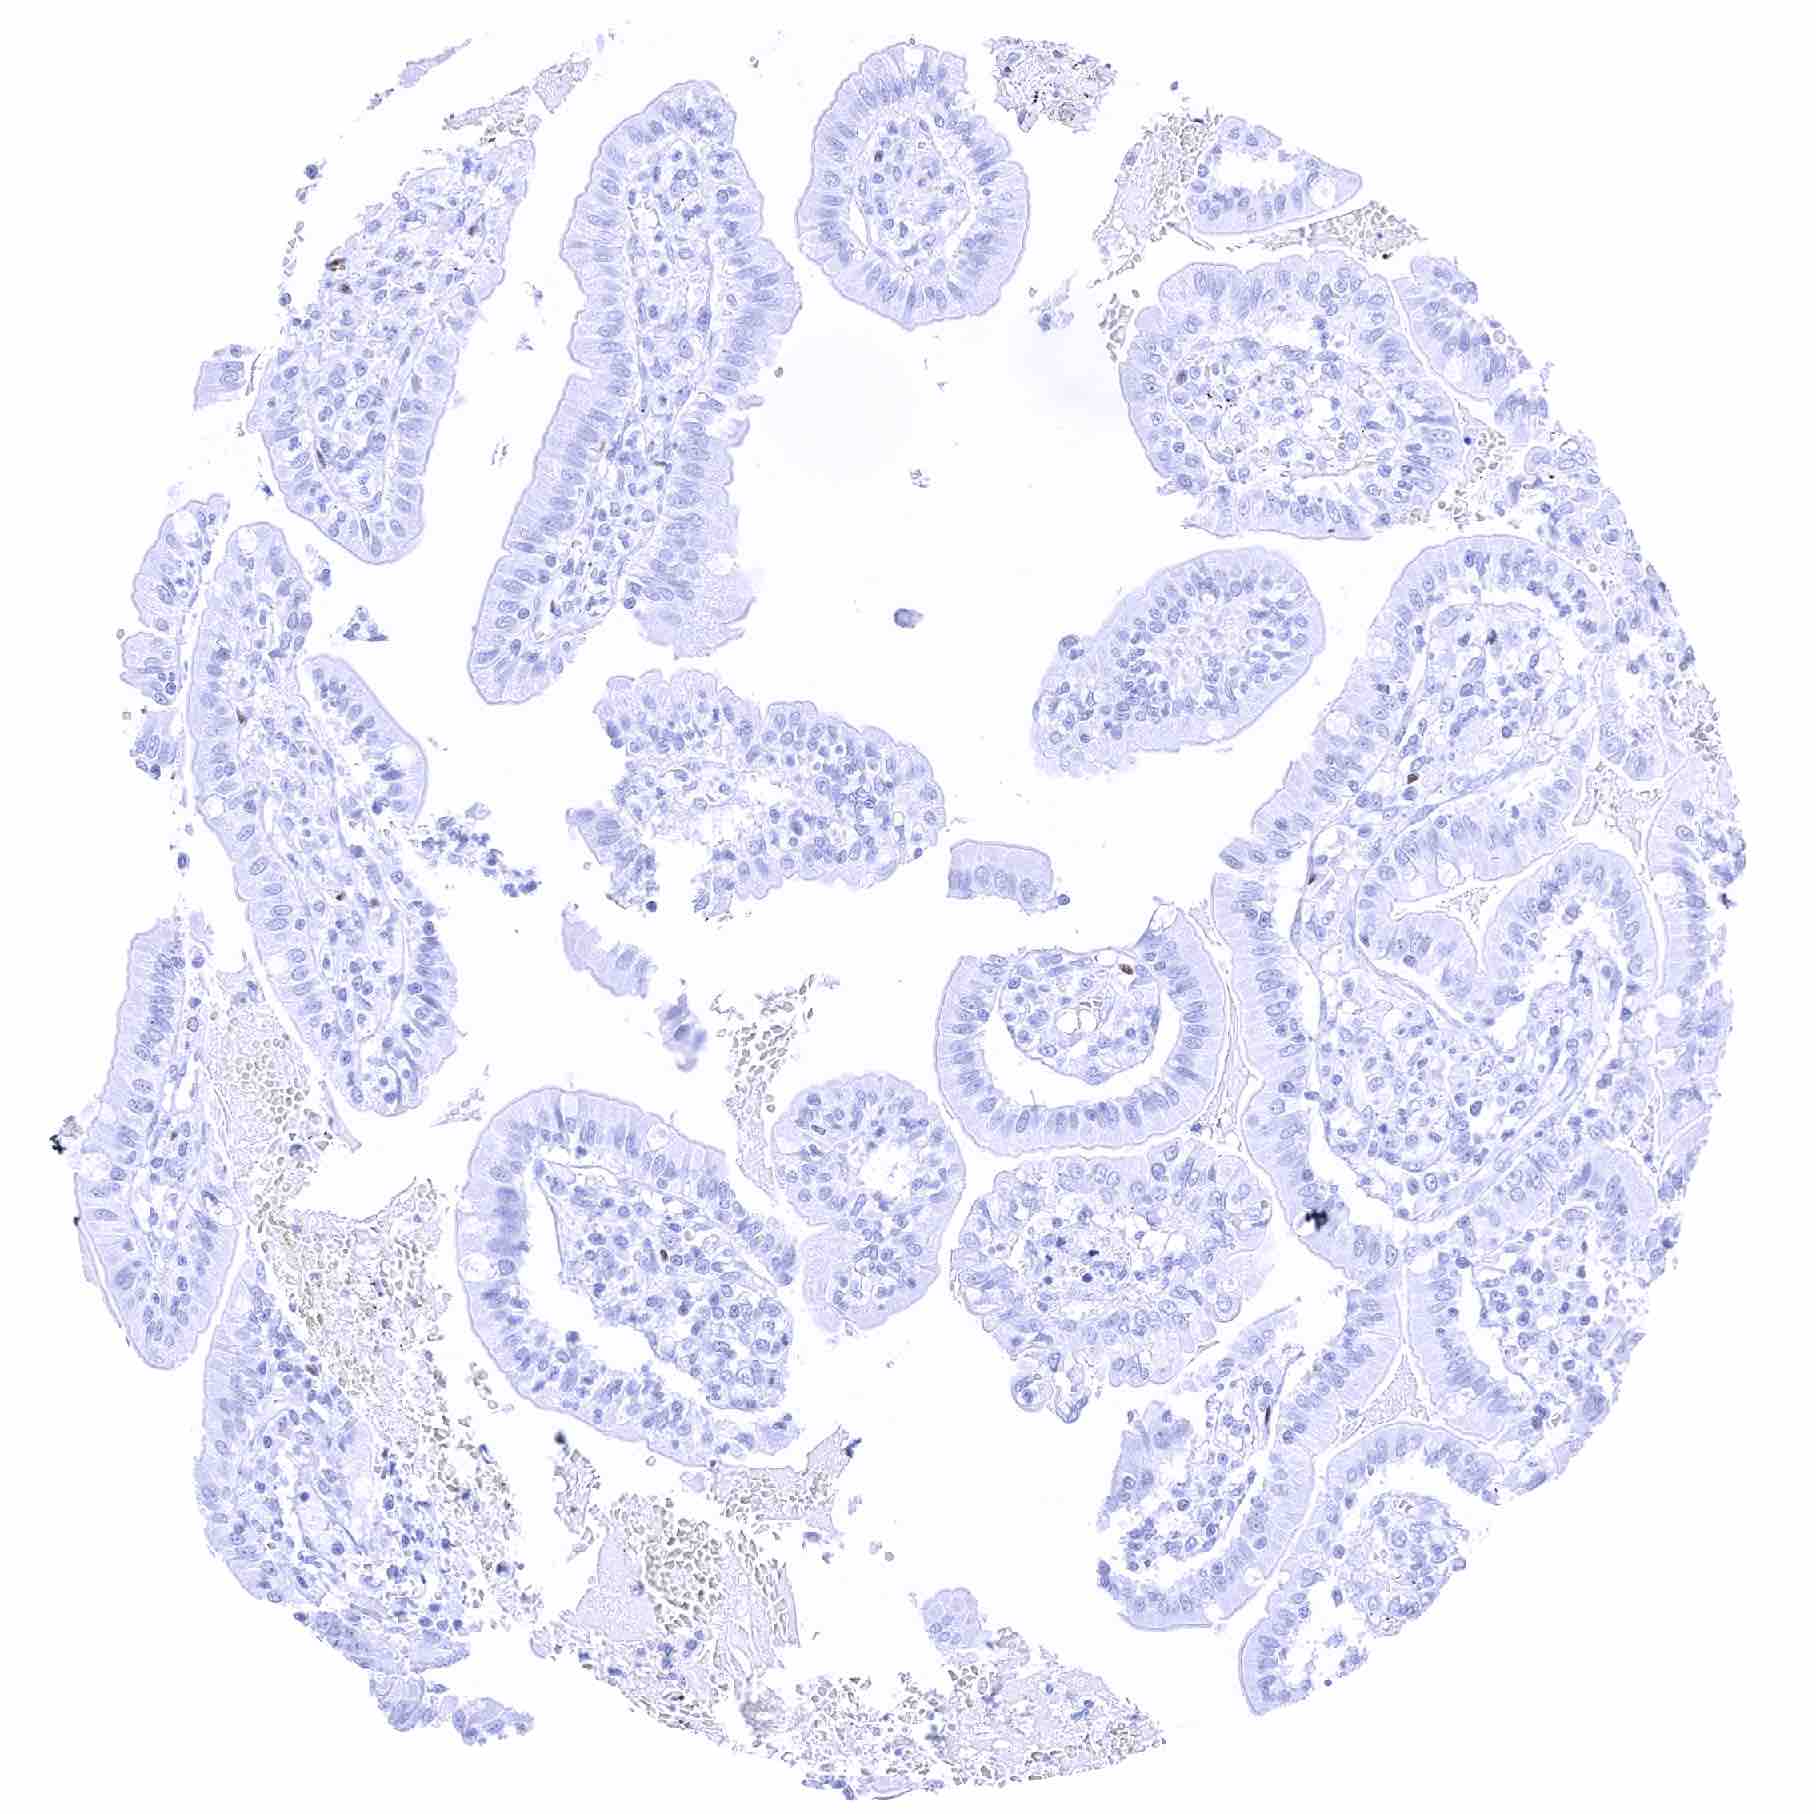

Duodenum, mucosa